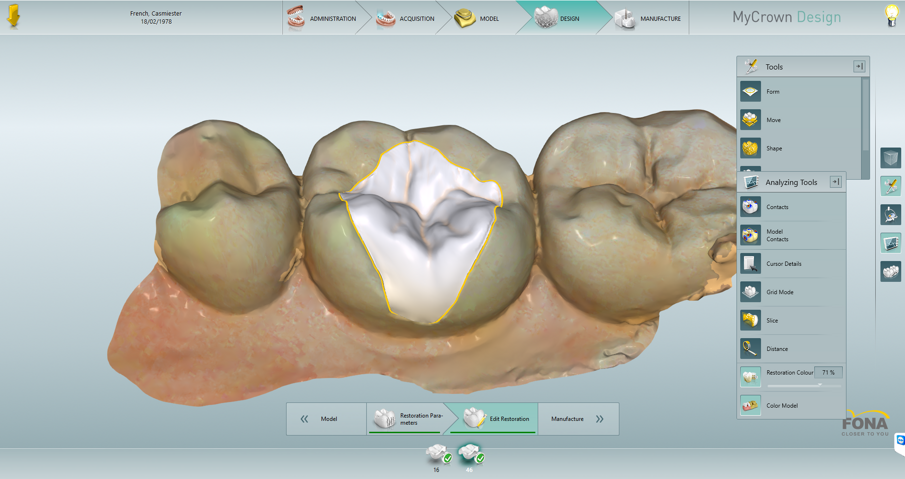

Having sprayed, then scanned each arch, then a buccal scan with the patient in centric occlusion, the MyCrown software correlated all the information and gave images of the upper lower and buccal scans. (Figs. 3, 4, 5, 6)

Choosing one prepared tooth first, the software asked me to create the restoration margin line. This is the yellow line, seen in the next two images. Then, moving to the other prepared tooth doing the same. Then moving to the next stage, the software gives an initial proposal for the restoration based on cusp height if the prepared tooth and those of the neighboring teeth.

Minor adjustments were made using the form tool which allowed me to add, remove and smooth small increments of tooth structure and volume to create a functional, non-traumatic occlusion with the restorations. There are various tools available to easily and extremely accurately modify the size and shape of the restoration if desired.